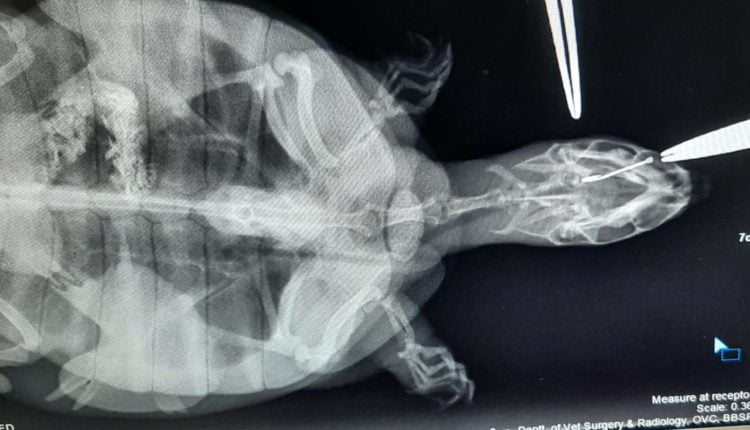

Professor Dr Indramani Nath of Veterinary Surgery and Radiology conducted X-ray to locate the position of the fishing hook, following which he was able to determine that it had not completely swallowed the fishing hook, and it was resting in its mouth. It took them 90 minutes to remove the hook.